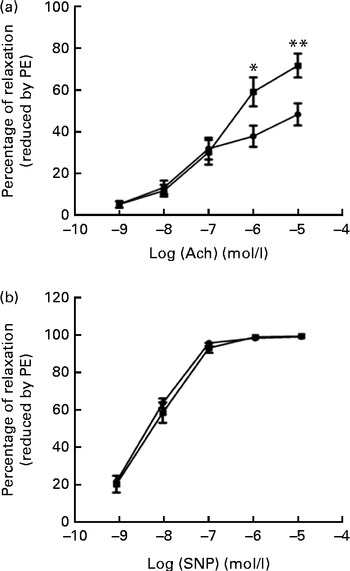

Relaxation response

We tested vascular function in mice using isometric tension studies. The endothelium-dependent arterial relaxation responses of the isolated thoracic aortic rings to endothelium-dependent acetylcholine (Ach) were measured. Compared with HFD-fed mice, FO supplementation resulted in an increased endothelium-dependent vasorelaxation response to Ach, indicating a significant improvement in endothelial function (P< 0·01; Fig. 2(a)). Endothelium-independent arterial relaxation in response to sodium nitroprusside did not differ between the two groups (Fig. 2(b)).

Fig. 2 Vascular reactivity. (a) Endothelium-dependent relaxation response to the increasing concentrations of acetylcholine (Ach). (b) Endothelium-independent relaxation response to sodium nitroprusside (SNP) in the thoracic aortic rings pre-contracted with 3 μm-phenylephrine (PE). Values are means (n 12), with standard deviations represented by vertical bars. Mean value was significantly different from that of the high-fat diet ![]() group: * P< 0·05, ** P< 0·01.

group: * P< 0·05, ** P< 0·01. ![]() , High-fat diet enriched with 10 % fish oil.

, High-fat diet enriched with 10 % fish oil.